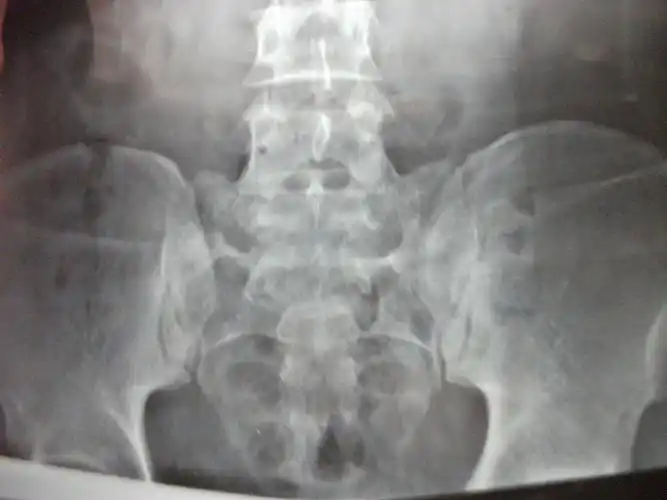

骶椎腰化,腰椎骶化在ct上如何诊断?放射科医生讲解!

男性患者47岁因腰骶不适摄片